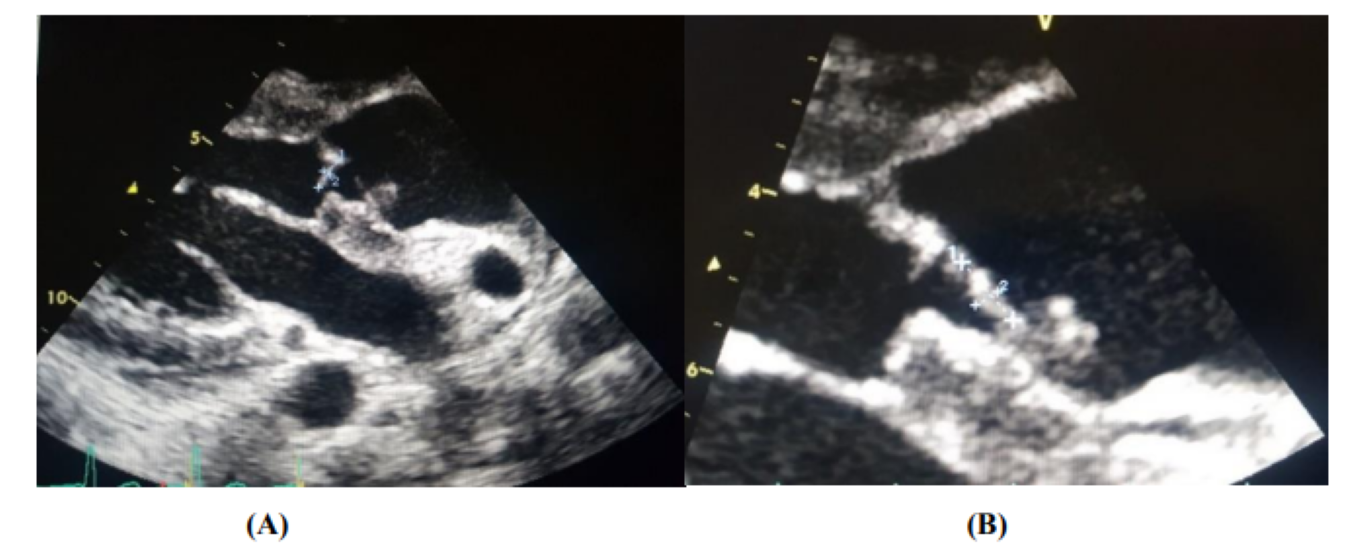

On transthoracic echocardiography, we find an aspect of valvular dilated cardiomyopathy with the presence of 2 vegetations at the level of the aortic valve (Figure 2), severe aortic insufficiency on the bicuspid aortic, and an aneurysmal dilation of the ascending aorta (52 mm), (Figure 3) complicated by an abscess collected at the level of the mitral aorto trigone and a 2nd abscess between the Left and Right cusps of the aortic valve fistulized into the aorta (Figure 4).

Figure 4: Perivalvular abscesses complicating an aortic IE [An abscess collected at the level of the aorto-mitral trigone (A, B) and a 2nd abscess between the Left and Right cusps of the aortic valve fistulized in the aorta (C)]